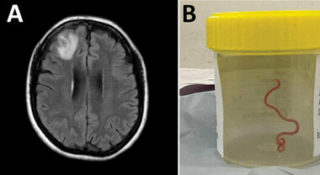

Larva viva dentro al cervello: rimossa da un neurochirurgo in Australia

A una paziente di 64 anni è stata trovata una larva dentro al cervello. La scoperta choc l’ha fatta Hari Priya Bandi, un neurochirurgo di un ospedale di Canberra, in Australia. Ha raccontato questa storia sorprendente un suo collega, un medico di malattie infettive, il dottor Sanjaya Senanayake.

“Oh mio Dio, non crederesti a quello che ho appena trovato nel cervello di questa signora: è vivo e lo vedo contorcersi”, questo – riporta il Guardian – è il sunto della telefonata ricevuta dal collega. La larva è poi stata rimossa: prima volta al mondo. Le foto sono poi state diffuse dalla rivista Emerging Infectious Diseases.